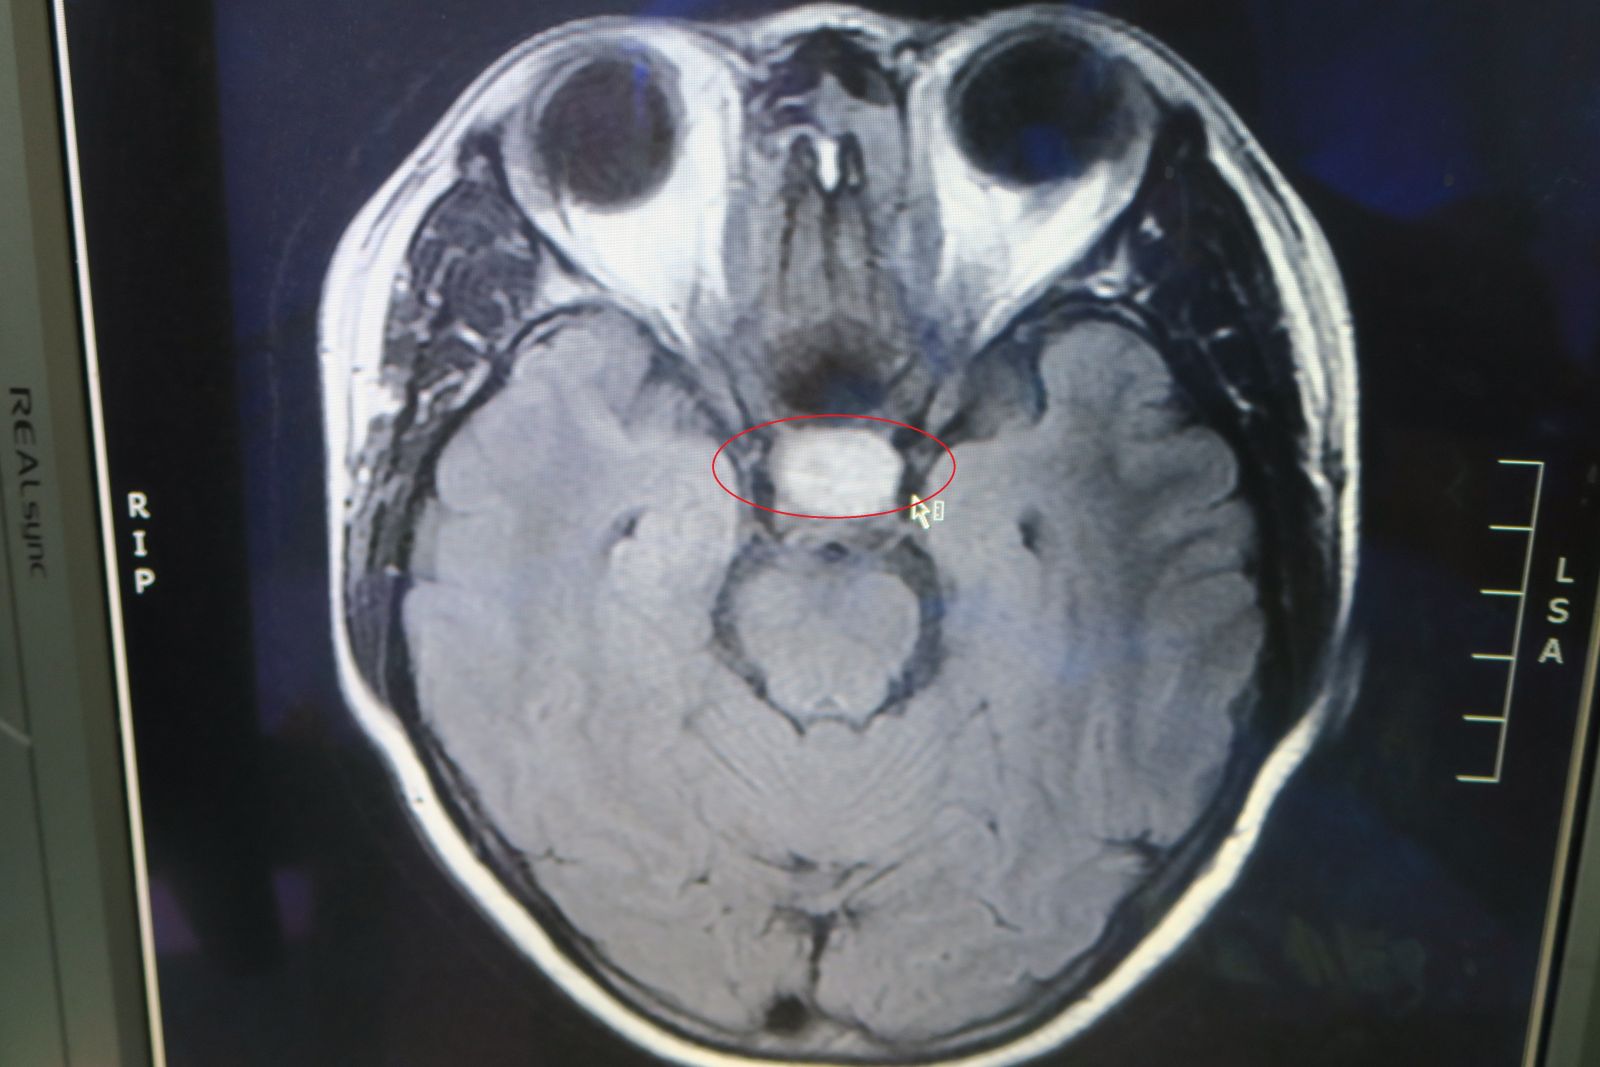

▲彰化醫院神經外科主任趙紹清發現謝女腦下垂體腫瘤變大,紅圈處為腦下垂體腫瘤。

謝女說,今年中旬她開始感覺到眼睛不對焦,兩側視野不見了,她一開始還以為是老花眼,調侃自己不到40歲就老了,但後來眼壓升高,眼睛痛並引起頭痛,還多次去按摩,但沒有改善,回醫院檢查才發現腦下垂體腫瘤變大,壓迫到視神經,才引起眼睛的諸多問題。

趙紹清說,經腦部核磁共振儀每年追蹤檢測患者,5年後患者的腫瘤已經大到2公分,還壓迫到視神經,進而影響視力,兩眼靠近外側的視野已經變小,一定要手術去除腫瘤,如果不處理,不僅生活中處處是危險,當神經壓迫越來越嚴重,眼睛還有可能失明,屆時再處理可能來不及了。